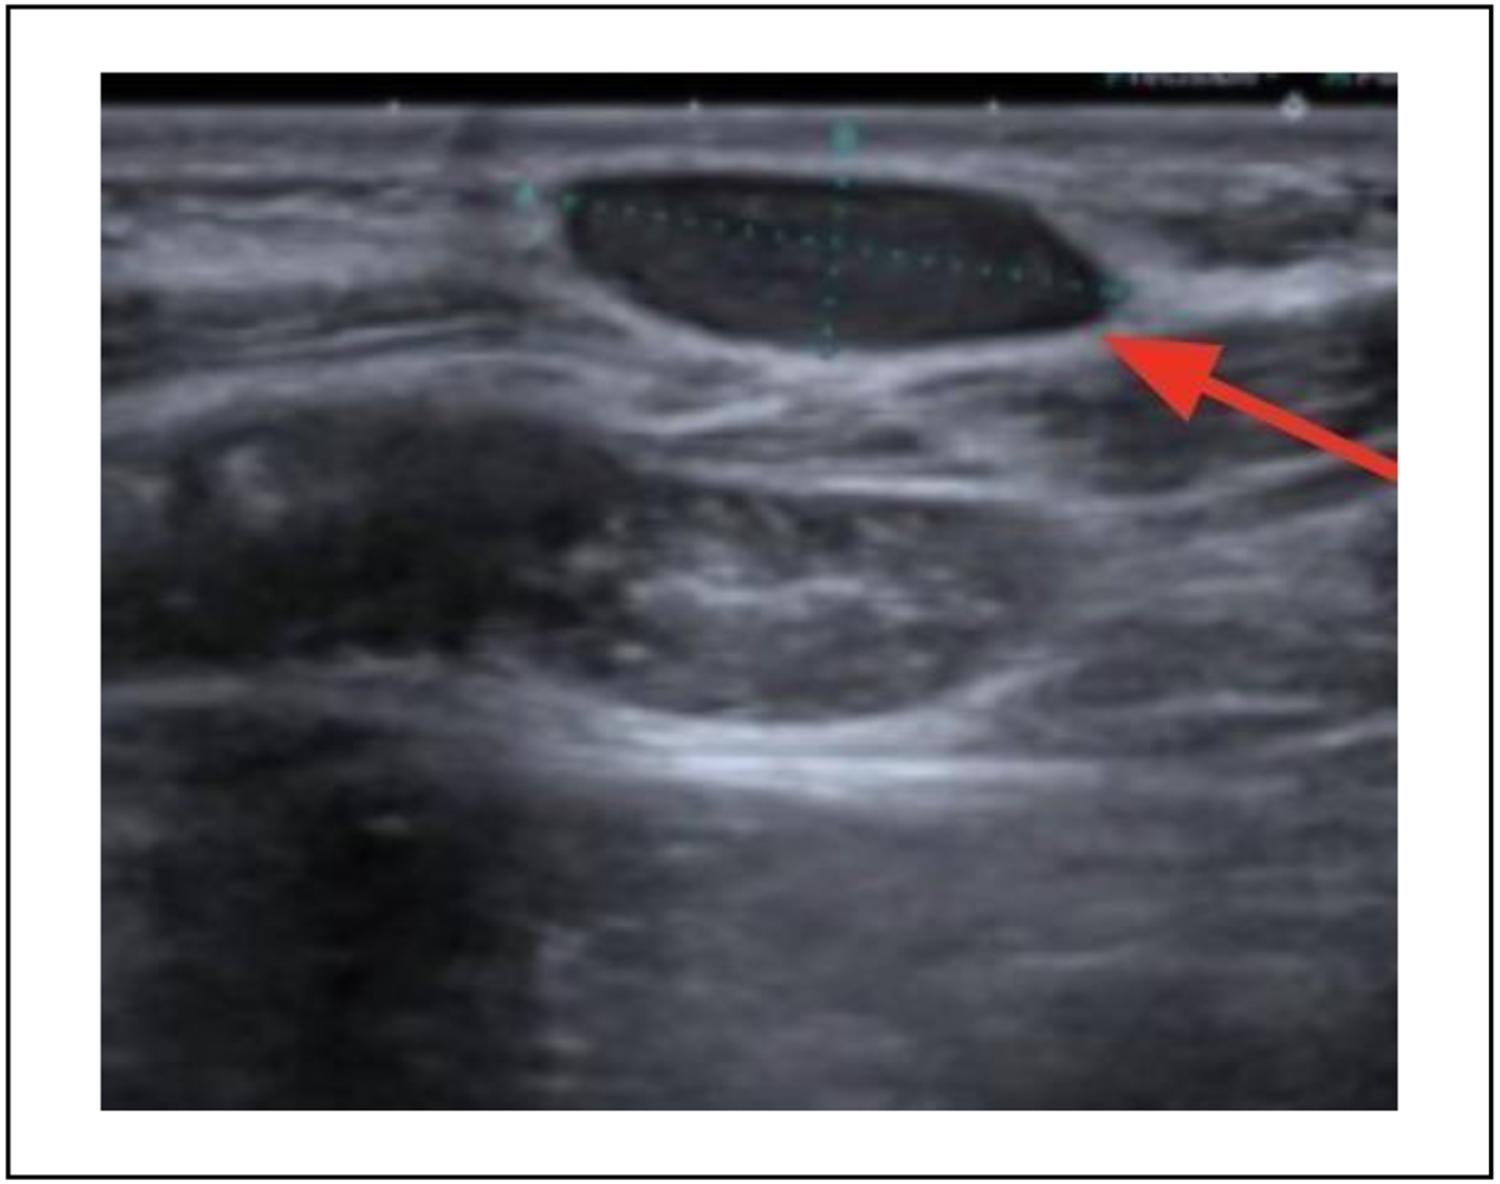

Se solicitó ecografía de partes blandas que planteó una esplenosis parietal de acuerdo con el antecedente quirúrgico (Figura 2).

Figura 2. Ecografía de partes blandas, esplenosis parietal (flecha roja).